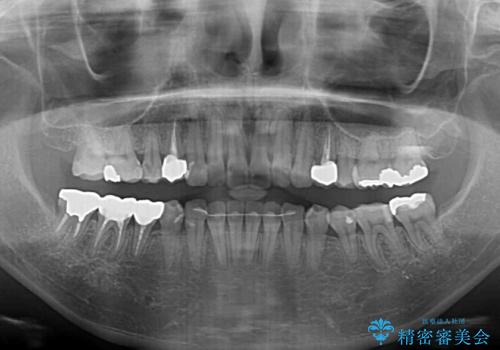

長時間のマウスピース装着と、患者様自身でのゴムかけに協力いただき、自然な口元に仕上げることができました。

気になっていた変色した歯もオールセラミッククラウンで本物の歯のようになり、患者様には大変満足していただきました。